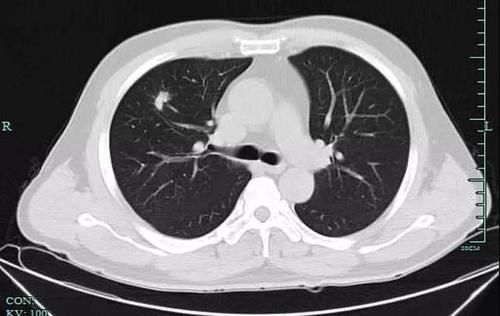

磨玻璃样结节

磨玻璃样结节是指肺内密度轻微增加,呈模糊的云雾状,但仍能通过病灶看到其内部血管和支气管纹理,就好像透过磨玻璃观察一样。

【 饭店生意越来越红火,“拼命厨娘”却查出了肺癌】磨玻璃样结节在临床上检出率很高,很多人对它的印象似乎都不友好,盛传它就意味着肺癌,事实上并不是所有的磨玻璃样结节都是恶性的,造成它的原因包括感染性病变、肿瘤等多方面,具体都需要经过医生的辨别与诊断。